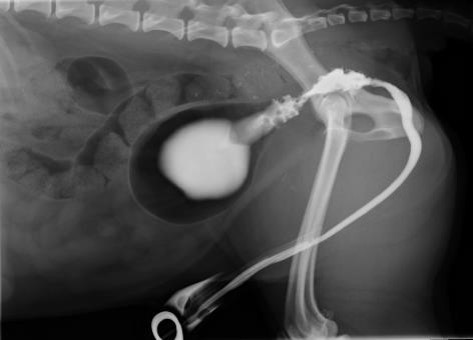

What has created this image?

What can be seen?

Pneumocystogram

Bladder normal – just displaced

Parenchymal cyst

You can see a mineral line and this is due to cyst cause mineralised lining (immediately puts this top of D/D)